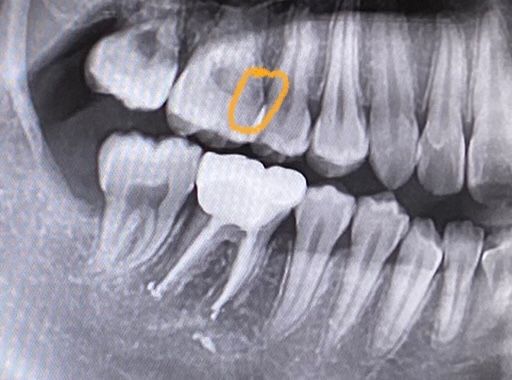

엑스레이로 충치인지 아닌지 판단 부탁드립니다.

엑스레이 상으로 보이는 어두운 부분이 충치인가요?

첫번째 사진의 치아는 겉으로 보기에 이상 없는데 엑스레이엔 어두운 부분이 있어요. 충치인가요?

만약 충치라면 어떤 치료 방법이 있을까요?

첫번째 사진의 치아처럼 충치가 법랑질이 아닌 상아질에서부터 진행될 수도 있나요?

사진상으로 보아서는 충치일 가능성이 매우 큽니다. 충치라면 해당 부위까지 치질을 제거해야 합니다. 다만 파노라마 사진은 3차원적인 자료를 2차원으로 반영하기 때문에 상당 부분이 왜곡될 수 있어 정확한 판단을 위해서는 임상 검사도 같이 해야 합니다.

저부위가 무조건 충치라고 말씀드리기는 어려울것같습니다. 일단 육안으로도 판단을 해봐야될것같습니다.만약 저부위가 충치가 맞다면 충치가 상당히 깊은곳에 위치하는것이며 충치를 제거하는과정중에 신경이 뚤리면 신경치료를 해야될 가능성이 높습니다.